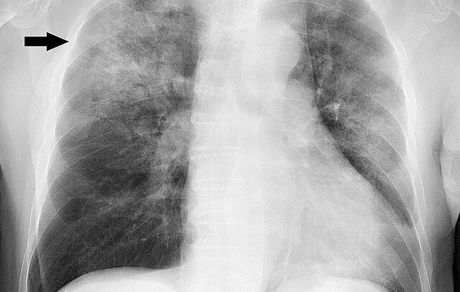

هر ساله در تاریخ ۱۲ نوامبر "روز جهانی ذاتالریه" گرامی داشته می شود.